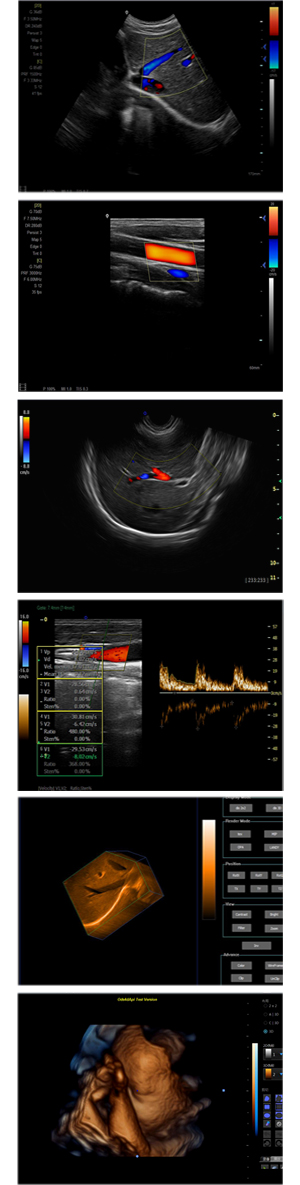

XF-7800型,秉承先鋒彩超技術(shù)之精華,擁有高雅大氣的獨(dú)特外型,為最新一代應(yīng)用型數(shù)字彩色多普勒診斷系統(tǒng),魅力與實(shí)力相融合。可廣泛適用于腹部、婦產(chǎn)科、心臟、小器官、乳腺、肌骨及外周血管等諸多方面的診查,讓您在臨床超聲診斷應(yīng)用領(lǐng)域得心應(yīng)手,綻放異彩!

突破的成像技術(shù)

● 3D/ 4D成像技術(shù)/限7800選配

● 應(yīng)用于腹部、腎臟、泌尿系統(tǒng)、產(chǎn)科、婦科、盆腔、大動(dòng)脈、肌肉組織、小器官、乳腺、心臟等

● 能量多普勒成像(PDI)

● 彩色血流量圖(CDE)

● 脈沖頻譜多普勒成像(PW)